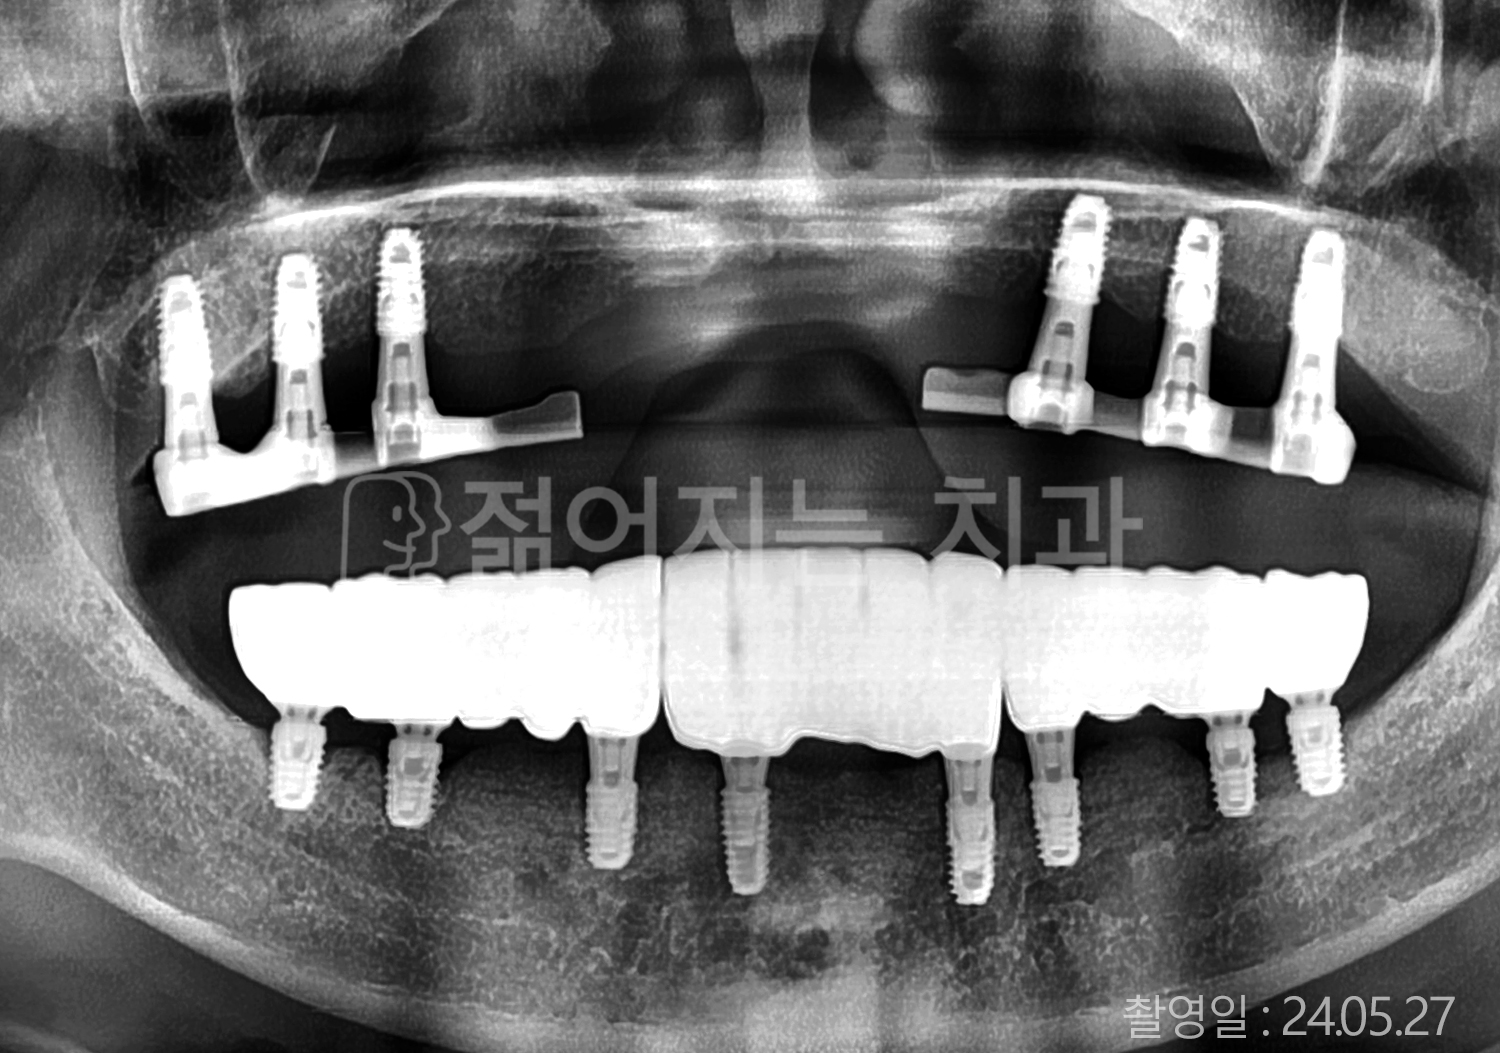

• 70대 고혈압, 고지혈증 전체치아 10개 이상 임플란트

• 60대 당뇨, 간염 전체치아 10개 이상 임플란트

• 80대 골다골증 전체치아 6개 이상 임플란트

• 70대 고혈압, 당뇨 전체치아 10개 이상 임플란트

• 60대 간 질환 전체치아 10개 이상 임플란트

• 60대 전체치아 10개 이상 임플란트

• 70대 전체치아 10개 이상 임플란트

• 50대 전체치아 10개 이상 임플란트

• 60대 고혈압, 고지혈증 전체치아 10개 이상 임플란트

• 40대 고지혈증, 뇌혈관 질환 전체치아 10개 이상 임플란트